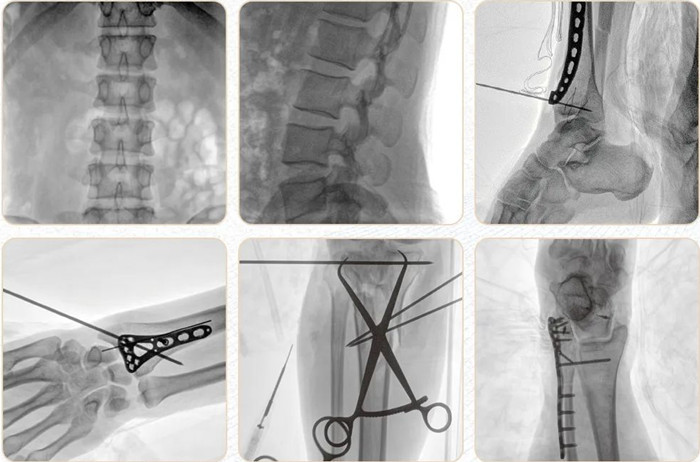

移动式平板C形臂PLX118F-Plus临床应用范围:可应用在骨科、普通外科、矫形外科、创伤外科、泌尿外科、脊柱外科、疼痛外科、消化科、肿瘤科、妇产科等科室。

普爱医疗移动式平板C形臂Plus系列搭配高端进口平板探测器,更高的空间分辨率让临床图像更加清晰锐利,更高的密度分辨率让不同组织的图像层次分明,更强的信号处理能力可以让设备用更低的剂量即可呈现优质的图像。